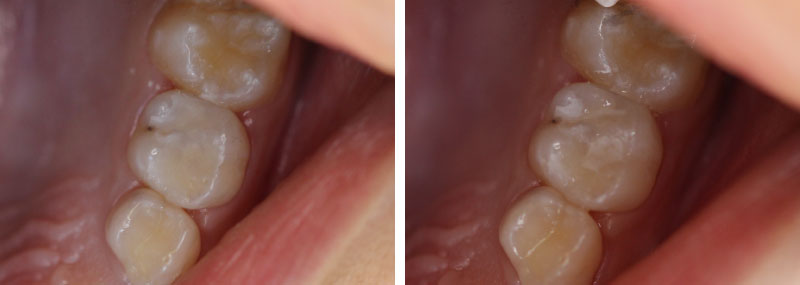

Paciente do sexo masculino, 7 anos de idade, compareceu ao consultório acompanhado pela mãe que se queixava de lesões de cárie nos dentes de seu filho. Após anamnese, exame clínico e radiográfico observou-se presença de lesão de cárie no elemento 65.

Para a resolução do caso foi proposta restauração com cimento de ionômero de vidro modificado por resina encapsulado (RIVA light cure cor A2).

Ao final da restauração, realizou-se ajuste oclusal e acabamento com pontas de silicone.

Ao final do tratamento foi possível observar técnica simples, realizada apenas com isolamento relativo que resultou em restauração satisfatória com boas propriedades mecânicas e estéticas.